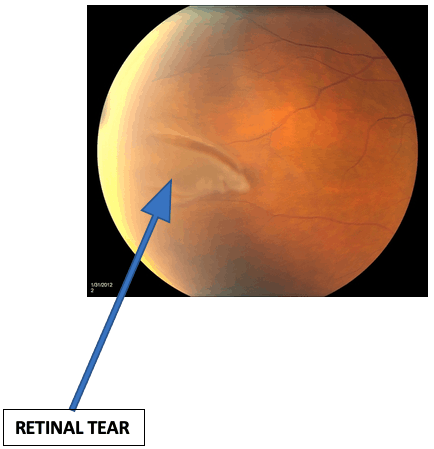

What are Retinal Tears?

The retina is a sheet of light-sensitive cells responsible for receiving light signals so we can see. The retina is attached to the inner wall of the eye.

The vitreous gel is a gel-like substance that is attached to the retina. Over time, the vitreous gel shrinks and becomes watery.

As the vitreous gel shrinks, it can pull on the retina causing a retinal tear.